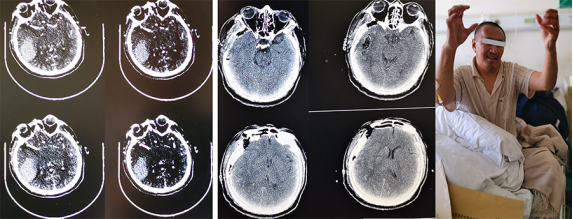

凌晨,一位来自西藏那曲的大叔,紧急急诊入院。入院时已然意识昏迷,呼之不应,查体不合作。头颅CT及CTA提示右侧颞叶大面积出血,出血量估计在40ml左右,脑干已经有受压征象,手术指征明确。

当我仔细查看急诊增强CT片时,发现血肿病灶内的增强点征——目前被认为是血肿继续扩大的金指标。如果不做手术,患者较大可能会出现严重神经系统并发症甚至死亡。

接下来,就是我们的主场,急诊行血肿清除术,术中探查发现血肿量确实比预估量的增加了一半多。术毕送走患者,完全松懈下来,才感觉到缺氧带来乏力和疲倦。所幸患者救治及时有效,复查CT血肿清除彻底。

出院时患者语言功能无大碍,左侧肢体活动力量已经有所改善。我们在给患者留影时,他漏出了略显僵硬的笑容,毕竟神经功能损伤还需要进一步康复,不过生活自理已不成问题。